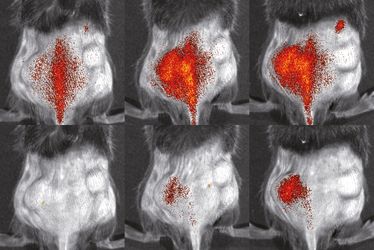

Verteilung von Immunzellen (rot) im Körper einer Maus mit einer entzündungsbedingten Hautkrankheit. Oben: genetisch unveränderte Zellen; unten: Zellen, denen das Protein VLA4 fehlt. Jeweils 3 Stunden (li.), 24 Stunden (Mi.) und 48 Stunden (re.) nach Injektion der Zellen (Abb.: S. Gran and L. Honold et al./Theranostics 2018(8))

Münster (upm) - Es ist ein komplexer und zugleich beeindruckender Prozess, den der Körper bei Entzündungen in Gang setzt. Die Hauptrolle dabei spielen Immunzellen, die sich aus dem Blut ins Gewebe aufmachen, um die Entzündung zu bekämpfen. Sind zu viele dieser Zellen aktiv, können sie umgekehrt aber auch Schaden anrichten. Mehr über ihr Verhalten herauszufinden, kann Wissenschaftlern als Basis dafür dienen, individuelle Entzündungstherapien zu entwickeln – zum Beispiel Zellen zielgerichtet an den Entzündungsherd zu leiten oder eine Therapie rechtzeitig wieder abzusetzen. Forscher des Exzellenzclusters „Cells in Motion“ der Universität Münster haben nun eine Methode entwickelt, mit der sie die Aktivität von Entzündungszellen in Mäusen besser beurteilen und untersuchen können: Sie schafften es, Vorläufer von Immunzellen genetisch zu verändern, anschließend im Reagenzglas zu vermehren und im lebenden Organismus mit verschiedenen Bildgebungsverfahren zeitlich und räumlich zu verfolgen. Dabei arbeiteten Immunologen und Spezialisten für molekulare Bildgebung interdisziplinär zusammen. Mit der neuen Methode können zudem Tierversuche deutlich reduziert werden. Die Studie ist in der Fachzeitschrift „Theranostics“ erschienen.Die Geschichte im Detail:Wenn der Körper einen Infekt abwehrt, sind es zunächst verschiedene Arten von „Fresszellen“, sogenannte Phagozyten, die nacheinander aus den Blutgefäßen ins Gewebe zum Entzündungsherd wandern. Sie erkennen Krankheitserreger, „fressen“ sie und töten sie ab. Unkontrolliert aktiviert können sie andererseits auch dafür verantwortlich sein, dass Krankheiten voranschreiten. Um die Wanderungsmechanismen von verschiedenen Phagozyten zu erforschen, untersuchen Wissenschaftler meist genetisch veränderte Mäuse, die entzündliche Krankheiten aufweisen. Das ist allerdings nicht einfach, da man hierfür eine große Anzahl an Immunzellen benötigt und viele Mäuse als Spendertiere gezüchtet werden müssen. Mit ihrem neuen Ansatz lösten die Immunologen um Prof. Johannes Roth, Gruppenleiter am Exzellenzcluster, nun dieses Problem: Sie nutzten immortalisierte Vorläufer von Knochenmarkszellen, die ERHoxb8-Zellen, welche sich im Reagenzglas nahezu unendlich vermehren und unter bestimmten Bedingungen zu Immunzellen ausdifferenzieren. So erhielten die Forscher am Ende eine hohe Anzahl verschiedener Typen von Phagozyten.„Unser nächstes Ziel war es, genetische Veränderungen der Zellen zu erzeugen, wie sie zum Beispiel bei angeborenen Immundefekten auftreten“, sagt Johannes Roth. Solche Mutationen betreffen häufig Proteine in den Membranen von Immunzellen, die ihnen dabei helfen, zum Entzündungsort zu gelangen. Eines dieser Proteine ist das VLA4. Was genau passiert, wenn es fehlt, können Wissenschaftler aber nur eingeschränkt untersuchen, weil sie die notwendigen Mäusestämme nur sehr schwer züchten können. Auch hierfür fanden die münsterschen Immunologen eine Alternative im Reagenzglas: Sie nutzten das molekularbiologische Verfahren der Genom-Editierung, um mithilfe von Enzymen den für das VLA4 relevanten Genabschnitt in den Knochenmarksvorläuferzellen gezielt „auszuschneiden“ und entsprechende „defekte“ Immunzellen zu erzeugen. „Durch unsere neue Methode können wir nun erstmals verschiedene Arten von Immunzellen beliebig genetisch verändern und wichtige Entzündungsmechanismen ausschalten“, sagt Dr. Sandra Gran, eine der beiden Erstautorinnen der Studie.Bildgebung mit optischen und nuklearmedizinischen Verfahren Die Bildgebungsspezialisten um Nuklearmediziner Prof. Dr. Michael Schäfers, Koordinator des Exzellenzclusters, markierten die so gewonnenen Zellen mit verschiedenen fluoreszierenden Farbstoffen, um sie in lebenden Organismen zu untersuchen – zunächst mit dem optischen Verfahren der Fluoreszenz-Reflektions-Bildgebung. Sie injizierten Mäusen mit einer entzündungsbedingten Hautkrankheit sowohl mutierte als auch gesunde Immunzellen und schafften es, die Wege der Zellen jeweils innerhalb desselben Tiers zu vergleichen. Dadurch konnten sie die Zahlen der Versuchstiere deutlich senken, denn normalerweise müssen für solche vergleichenden Untersuchungen verschiedene Gruppen von Tieren eingesetzt werden. Die neue Methode funktionierte: „Wir konnten sehr genau beobachten, wie unterschiedlich sich die verschiedenen Immunzellen verhielten. Zum Entzündungsherd schafften es etwa doppelt so viele gesunde Immunzellen im Vergleich zu den genetisch veränderten“, sagt Dr. Lisa Honold, ebenfalls federführende Autorin der Studie. Auf dieselbe Weise untersuchten die Forscher mit ihrem neuen Verfahren noch weitere Zellen, denen andere Membranproteine fehlten. In einem weiteren Schritt sahen sich die Wissenschaftler wandernde Immunzellen in Mäusen mit einem Herzinfarkt an. Solche Untersuchungen stellen naturgemäß eine große Herausforderung dar, da das Herz tief im Körperinneren liegt und sich beim Pumpen sehr schnell bewegt. Die Forscher nutzten ein nuklearmedizinisches Bildgebungsverfahren, mit dem sie digitale Schnittbilder aus tiefen Gewebeschichten herstellen können: die Einzelphotonen-Emissions-Tomographie, SPECT genannt. Sie markierten die Zellen im Reagenzglas mit einer radioaktiven Substanz, deren Strahlung gemessen und in Bildern sichtbar gemacht werden kann. Nachdem sie die Zellen Mäusen injiziert hatten, untersuchten sie, wo sich die markierten Zellen in verschiedenen Phasen des Infarkts aufhielten. „Durch die serielle Bildgebung können wir nun das Verhalten von Immunzellen über einen langen Zeitraum verfolgen“, sagt Nuklearmediziner Michael Schäfers. Auch das soll dazu führen, die Zahlen der Versuchstiere zu senken, weil herkömmliche molekularbiologische Methoden lediglich Momentaufnahmen liefern und weitaus mehr Experimente erfordern.Die Wissenschaftler wollen ihre neue Methode auch in Zukunft in präklinischen Untersuchungen anwenden und weiterentwickeln – beispielsweise bei Infektionen, rheumatologischen und arthritischen Erkrankungen. Wann die Ergebnisse für patientenorientierte Anwendungen relevant sind, ist allerdings derzeit noch nicht absehbar.Die Studie entstand in einem interdisziplinären Flexible-Funds-Projekts von CIM. Darüber hinaus erhielt sie Mittel der WWU-Sonderforschungsbereiche 656 „Molekulare kardiovaskuläre Bildgebung“ und 1009 „Breaking Barriers“ sowie des Interdisziplinären Zentrum für klinische Forschung der Medizinischen Fakultät Münster. Das Bundesforschungsministerium förderte die Studie ebenfalls.Link zur Publikation